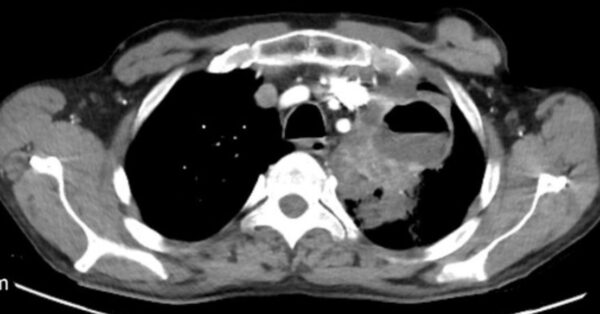

Case 64

https://radiopaedia.org/cases/pulmonary-abscess-7

Modality

CT

Region

CHEST